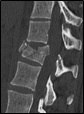

- T.A.C. (Escáner)

Es una prueba no invasiva, pero más cara y menos accesible que las radiografías. La dosis de radiación (Rayos X) que se recibe es alta. Diagnostica muy bien problemas de los huesos y menos de los tejidos adyacentes. En la actualidad se pueden obtener imágenes en 3 dimensiones que nos ayudan a comprender mejor el estado de las vértebras. Puede utilizarse como guía para obtención de biopsias, cultivos, etc. Su uso se reserva al médico hospitalario.